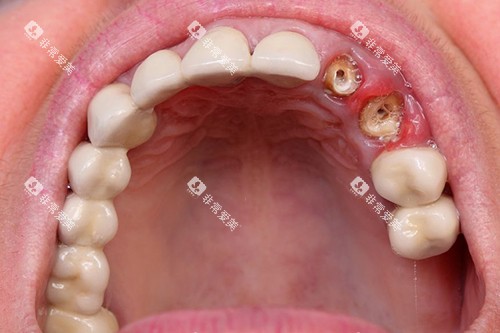

当牙齿龋坏重的,累及牙髓时,就需要进行根管治疗。

根管治疗的收费与牙齿的部位和根管数量有关。

前牙的根管治疗相对简单,一般一个根管的治疗费用在 300 - 500 元左右。

前牙通常只有一个根管,所以单颗前牙的根管治疗总费用大概在 300 - 500 元。

后牙的根管数量较多,一般有 2 - 4 个根管,每个根管的治疗费用在 400 - 600 元左右。

因此,单颗后牙的根管治疗总费用在 800 - 2400 元不等。